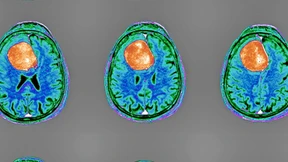

Hirntumoren sind sehr schwierig zu behandeln. Moderne Impfungen und altbekannte Wirkstoffe könnten eine Wende bringen. Sofern man die Tumoren genau identifiziert.